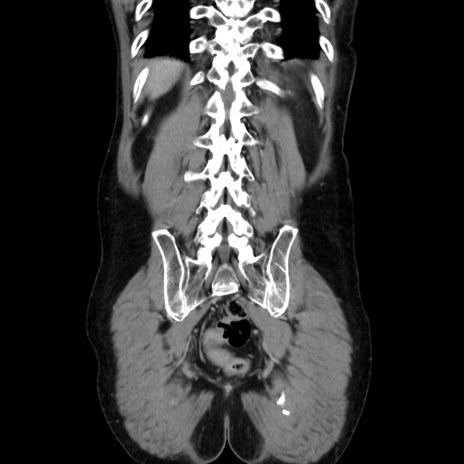

症例37(冠状断像)

【症例】40歳代 男性

【主訴】腹痛

【現病歴】4時間ほど前に電車に乗車中に臍部上より腹痛出現。徐々に増悪し起立困難となり、救急外来受診。生ものは数日食べていない。今朝お雑煮を食べた。

【身体所見】BT 36.8℃、BP 117/84mmHg、HR 91/min、SpO2 97%、苦悶様、腹部:臍上部広範囲圧痛あり、反跳痛±

【データ】WBC 8100、CRP 0.03